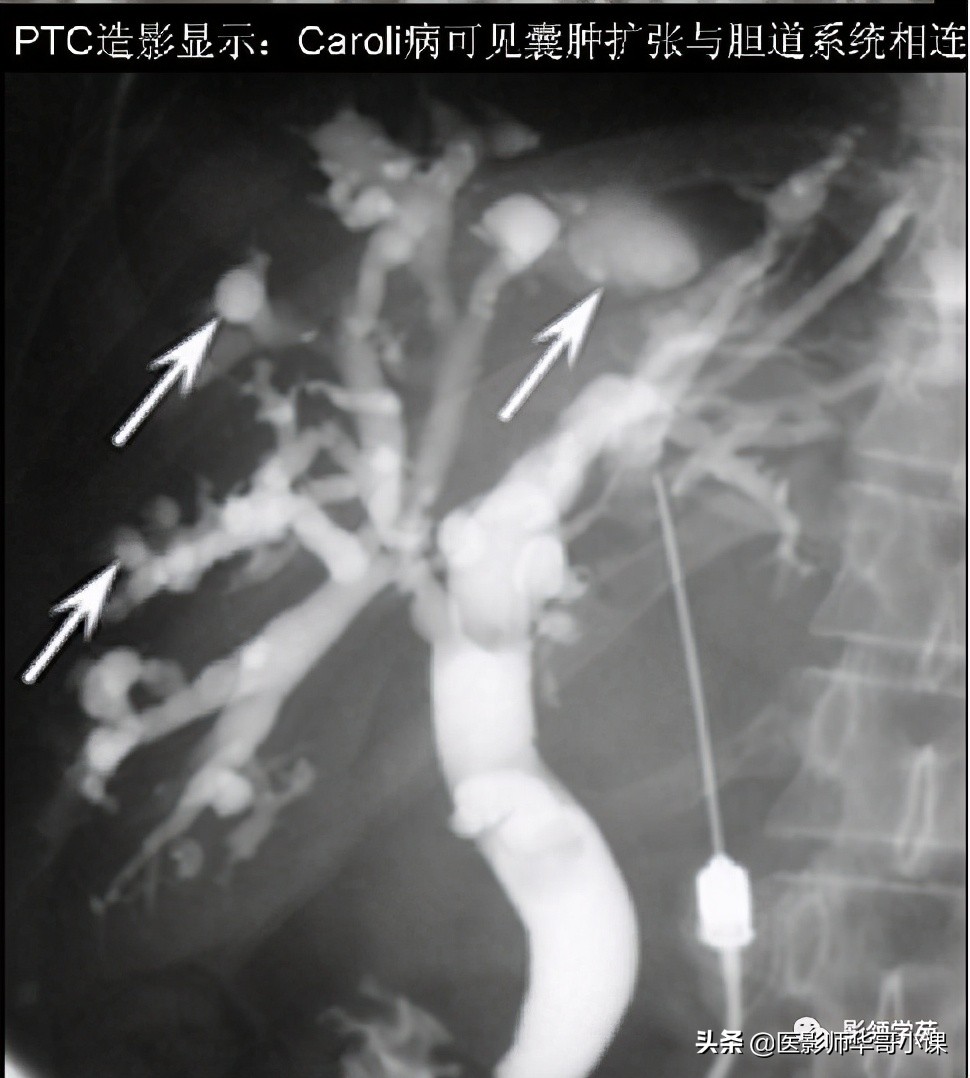

Caroli病 其他检查

- 经皮肝穿刺造影 (PTC):因PTC是有损伤性的检查,现临床上已较少应用。